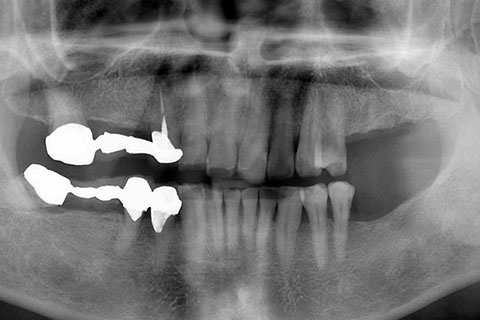

症例2

治療前

インプラント埋入時

治療後

- 年齢・性別

- 57歳男性

- 治療期間

- 3ヶ月

- 抜歯

- なし

- 治療費

- 154万円

- 備考

- 左上5.6.7 及び左下6.7欠損

- 治療内容

- 左上5.6.7と左下6.7欠損部にインプラント埋入

- 施術の副作用(リスク)

- オペによる知覚障害。インプラントによる歯肉炎。インプラント脱落。